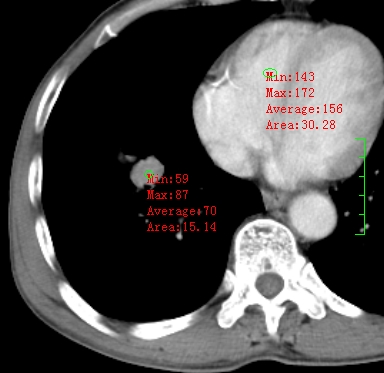

m,73y。膝关节疼痛伴双下肢水肿。入院常规胸片发现结节灶。增强为静脉期。

指套征,强化明显,近侧肺组织局限性肺气肿,考虑支气管类癌,慢支、肺气肿、双上陈旧性tb、冠脉钙化。

鉴别:先天性支气管闭锁,变态反应性支气管肺曲霉菌病,肺癌,支气管囊肿,支扩黏液嵌塞。